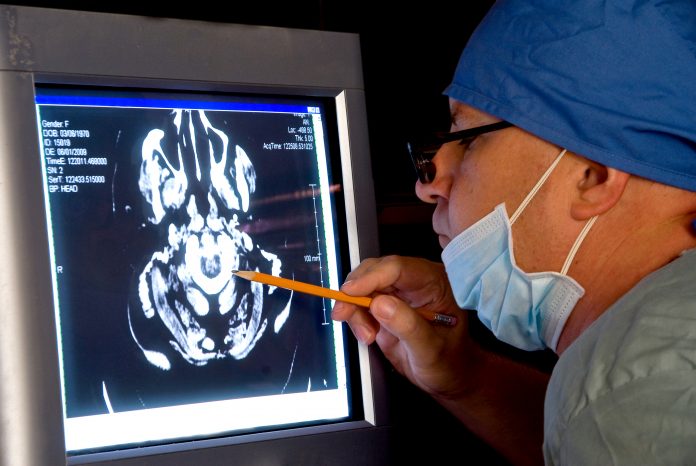

Figure 4 presents the case of a woman who sustained a mTBI in a rear-end car accident (without loss of consciousness). At the ED, CT imaging of head was normal and she was sent home. Unfortunately, she developed PPCS and sought neurologic opinion six months following the accident. An MRI of her brain was normal. Her PPCS symptoms persisted two more years. Brain SPECT imaging then revealed significant metabolic rCBF abnormalities underlying her PPCS. Studies have consistently demonstrated the superior sensitivity of functional imaging, such as SPECT and/or PET over CT and/or MRI to evaluate mTBI in the chronic setting. (10,11)